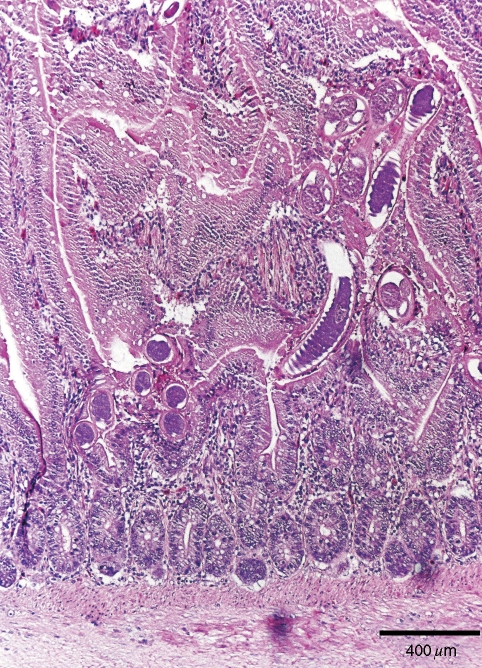

Histopathologically, most lesions caused by capillarid parasites were observed in the duodenum in both birds where most adult Capillaria were found (Fig. 4). The thin anterior ends of many adult Capillaria worms invaded into the mucosa between the villi and burrowing into the lamina propria, while the posterior ends of many of the parasites extended into the lumen of the intestine (Fig. 4). Lamina propria showed usually moderate-to-severe infiltration of lymphoid cells with some heterophils. The number of goblet cells was increased in the villi of the small intestine. Occasional distension of the glands of Lieberkühn with mucus and/or heterophils was also observed.